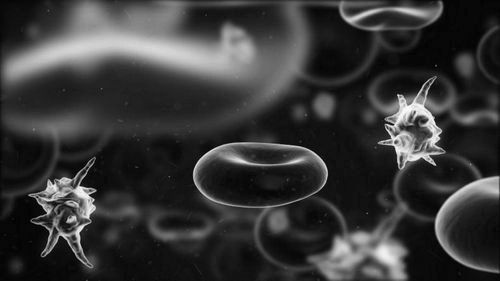

Залежно від виду наркотику, діюча речовина може впливати на різні органи і системи людського організму.

Опіатні препарати мають седативну дію, загальмовують діяльність нервової системи людини. Впливають на обмінні процеси, викликаючи швидку появу залежності. Викликають руйнування всіх систем організму. До таких препаратів відноситься героїн, метадон, макова соломка, опій-сирець.

Наркотичні речовини з конопель впливають на психіку, викликаючи у наркомана галюцинації, загальмованість мислення, психічні хвороби. Отруйний дим впливає на стан легенів, слизової рота, зубів. До цієї групи належить марихуана і гашиш.

Амфетаміни мають стимулюючу дію, підстьобують нервову систему і обмін речовин, змушуючи їх працювати «на знос». Це синтетичні препарати, з яких найбільш відомі первітин, ефедрин.

Через впливу кокаїну тіло стає нечутливим, діюча речовина відключає нервові рецептори, які відповідають за відчуття.

Наркотики поступово руйнують організм. Порушується робота мозку, людина відчуває труднощі при розумової діяльності, стає агресивним, впадає в істерики. Серцево-судинна система і серце через кілька років прийому наркотиків у молодої людини зношується, як у старого. Отруйний дим викликає рак легенів або захворювання ротової порожнини. Вживання наркотиків порушує репродуктивну функцію, викликаючи безпліддя або народження дітей з відхиленнями. Знижується імунітет, підвищується ризик зараження багатьма захворюваннями. У середовищі наркоманів поширені такі хвороби, як гепатит і СНІД. Статистика показує, що люди, які регулярно вживають наркотики, живуть не більше 7-10 років.